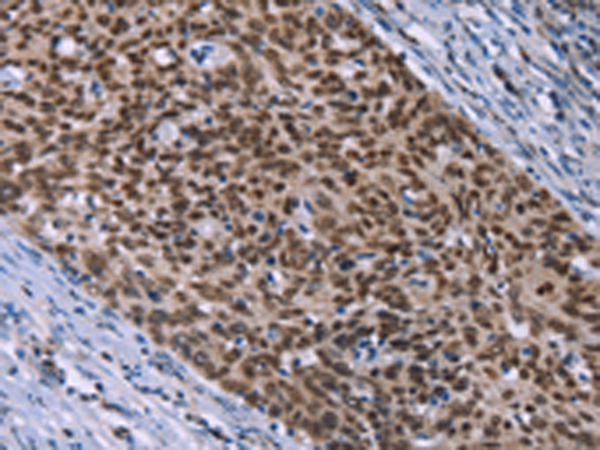

分类: 科研抗体货号: P03901别名: SEK, HEK8, TYRO1应用: IHC反应种属: Human, Mouse